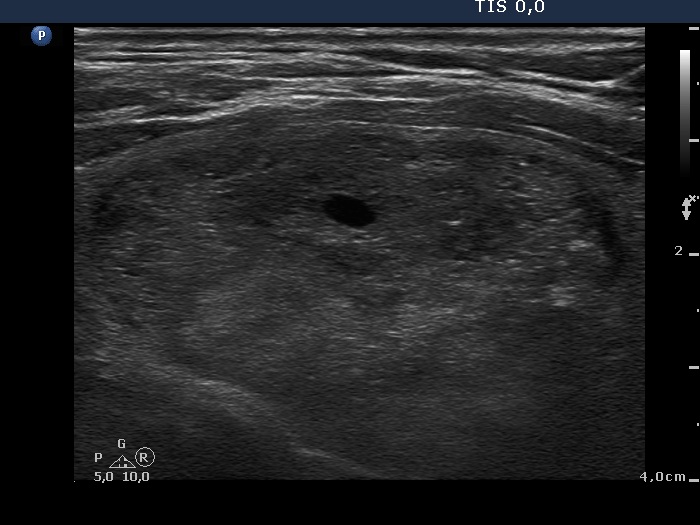

Ultrasonography. The right thyroid was intact. A large nodular area occupied almost the entire left thyroid. It was composed of moderately hypoechogenic, cystic, echonormal and hyperechogenic discrete lesions. The whole lesion was surrounded with an incomplete halo and presented a type 2 vascular pattern.

The sonographic pattern, i.e. a large nodular area composed of discrete lesions with different echogenicity is characteristic of a benign, hyperplastic nodule.